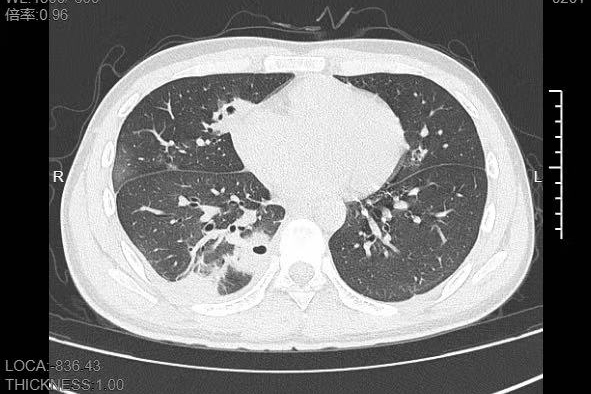

熬到第三天,小林已经烧到39℃,赶紧来到宁波大学附属第一医院就诊。接诊的呼吸与危重症医学科丁群力主任医师一看他的症状,立刻安排了CT检查。结果显示:小林的肺里有十几个空洞,部分肺组织已经坏死,这是典型的血源性肺脓肿。

像小林这样,当细菌跑到肺组织上后,就会开始疯狂破坏肺细胞,引发局部炎症。随着炎症加重,肺组织会逐渐坏死、液化,最终形成一个个空洞。